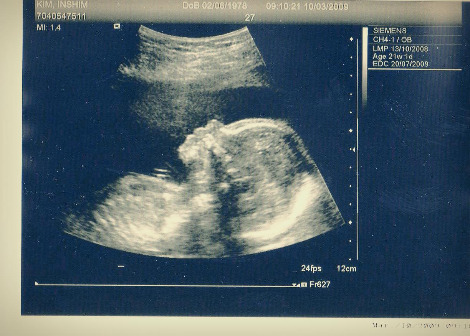

몇 달 전 아내의 임신 소식을 듣고 생애 처음으로 느껴지는 특별한 감정이 있었다. 그 여운은 여전히 내 가슴 깊은 곳에서 감돌았고 나의 얼굴은 상기되어 있었다. 볼록해진 아내의 아랫배 위에 초음파 탐촉자가 가로선을 그리며 보물을 찾아내듯 조심히 움직였다. 흑백 화면 속에 비치는 흐릿한 아기 형상을 보고 있을 때 아내를 잡고 있던 내 손에 힘이 들어갔다. 심장을 박동하며 살아 움직이는 작은 생명체가 있었다. 놀라운 광경에 입을 벌린 채로 모니터 상단에 적혀진 태아의 나이에 시선이 고정되었다. 21주 1일살.

img010.jpg 런던병원에서의 초음파